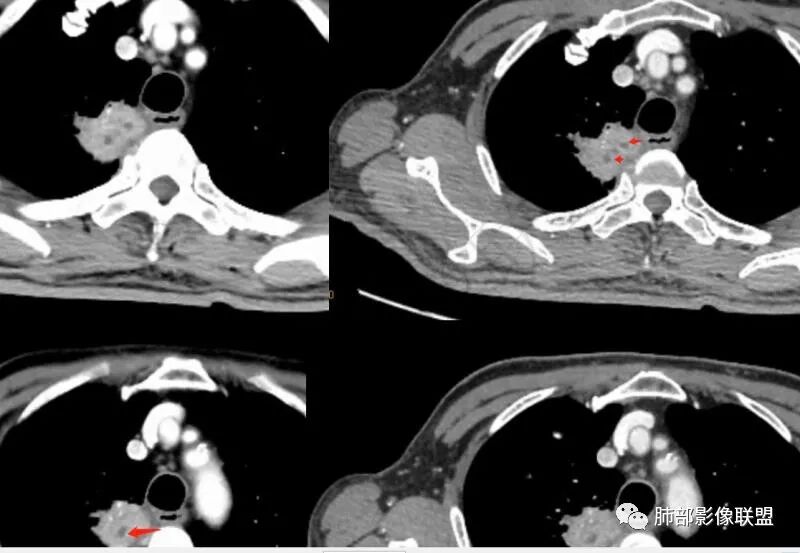

南边:捋一捋吧,老年男性,刺激性干咳10天,血沉稍高

右上叶尖段带状实变影

外围大、内带小,宽基底与胸膜相连,附近卫星灶

支气管进入病灶内,广泛胸膜增厚

支气管粘液栓

血管走形自然

实变区强化较均匀,明显强化

边缘平直为主

支气管堵了,但是远端粘液栓:是粘液栓堵塞?还是狭窄或堵塞后继发粘液栓?

病灶是支气管腔内堵塞导致远端实变、不张?还是外围病灶融合、实变影响近端支气管?

整体考虑肿块应该不支持,因为支气管、血管走形还算自然,只是收缩在一起,如果肿块走形不会这么自然,会推移、变形,侵犯

现有的图显示近端支气管还是连续的,只是远端扩张,腔内粘液栓,其实还应当看重建的支气管连续的图,与近端含气部分的连续